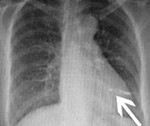

Рентгенография сердца позволяет идентифицировать рентгеноконтрастное инородное тело, уточнить его местоположение и размеры, установить количество, если имеется несколько объектов. По данным рентгенографии определяются размеры сердца, крупные сосуды, их положение, их форма, наличие патологических образований и их смещение.